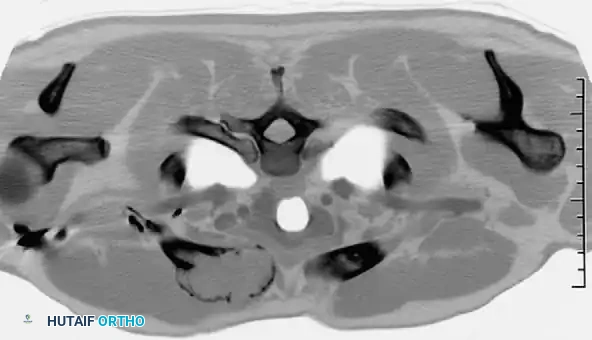

CT scan of a 39-year-old man demonstrating a destructive lesion of the right medial clavicle. Biopsy revealed a solitary plasmacytoma with abundant amyloid. While amyloid in bone is highly associated with myeloma, plasmacytoma and lymphoma share overlapping radiographic features and require definitive tissue diagnosis.